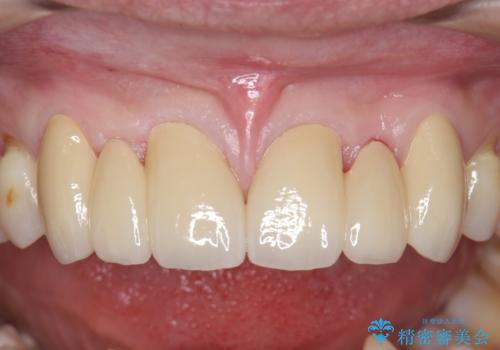

オールセラミッククラウン 部分矯正とセラミックによる前歯部の見た目の改善

- 前歯部のすきっぱと歯並びが気になるので診て欲しいといらっしゃった方の症例です。

全顎矯正は御希望されなかったため、上顎前歯部のみの部分矯正とオールセラミッククラウンによる補綴を行いました。

今回用いたオールセラミッククラウンはジルコニアフレームという白い素材の上にセラミックを盛っているため、審美性が非常に高いのが特徴です。

また、ジルコニアは人工ダイヤモンドの材料にも使われているほど高い強度を持っており、そのためオールセラミッククラウンは審美性だけでなく、奥歯やブリッジの補綴も可能とするクラウンです。